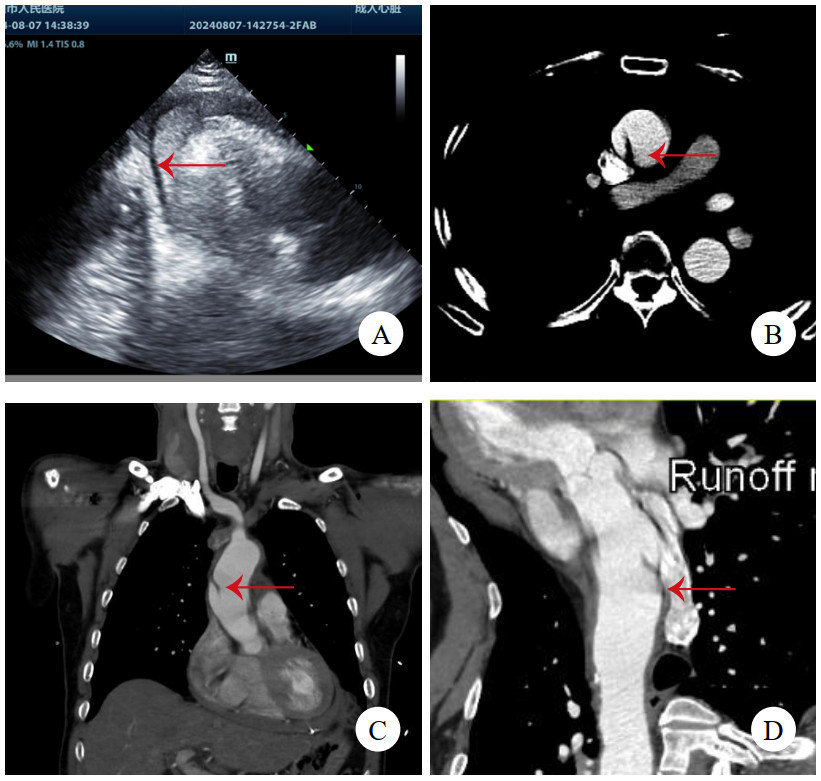

1 病例资料病例1,女,41岁,因“突发严重胸闷气促15 h”入院。发病后立即就诊于附近医院,查胸腹平扫CT提示急性肺水肿、双侧胸腔积液、心包积液,查血红细胞计数3.38×1012/L,肌酐369 μmol/L,乳酸11.7 mmol/L,钠尿肽超过检测上限,立即转诊至本院。考虑存在急性多脏器衰竭,立即收入重症监护室,因少尿予连续肾脏替代治疗。右侧胸腔穿刺引流液红细胞计数高达0.22×1012/L。床边经胸超声心动图(transthoracic echocardiography, TTE)未见主动脉病变,但见左心室弥漫肥厚符合高血压性心脏病,心包大量积液伴血块,且出现心包填塞,紧急行心包穿刺,但置管后引流不畅。因心包积液病因不明,且回顾前平扫CT可见升主动脉壁局部密度增高(图 1A),急查主动脉CTA,但影像科对升主动脉根部管壁褶皱情况考虑为搏动伪影。后查经食管超声心动图(transesophageal echocardiography, TEE),清晰可见升主动脉直径38 mm,距主动脉瓣环约16 mm处有飘动纤细光带,考虑升主动脉LIT(图 1B、图 1C)。遂行急诊开胸手术,术中见心包腔内大量积血并血块,升主动脉外膜血肿延入肺动脉外膜至右侧肺门。建立体外循环后,在头臂干开口近侧阻断升主动脉,顺行灌注心脏停搏液良好,纵行切开升主动脉,见左右冠瓣上方横行内膜裂口,中膜无假腔形成,冠状动脉开口、主动脉瓣无病变。用26 mm人工血管置换升主动脉,手术顺利。术后复查TTE见人工血管通畅、形态良好。回顾并重建术前主动脉CTA,曲面重建可见内膜片(图 1D),该处主动脉直径为37 mm。患者术后肾功能衰竭持续,规律随访血透,6个月后失访。

| 注:A为平扫CT,箭头示升主动脉壁增厚、密度增高;B为TEE舒张期,箭头示飘动纤细光带;C为TEE收缩期,箭头示飘动纤细光带;D为主动脉CTA,曲面重建,箭头示内膜片 图 1 例1患者两次CT及术前TEE影像 |